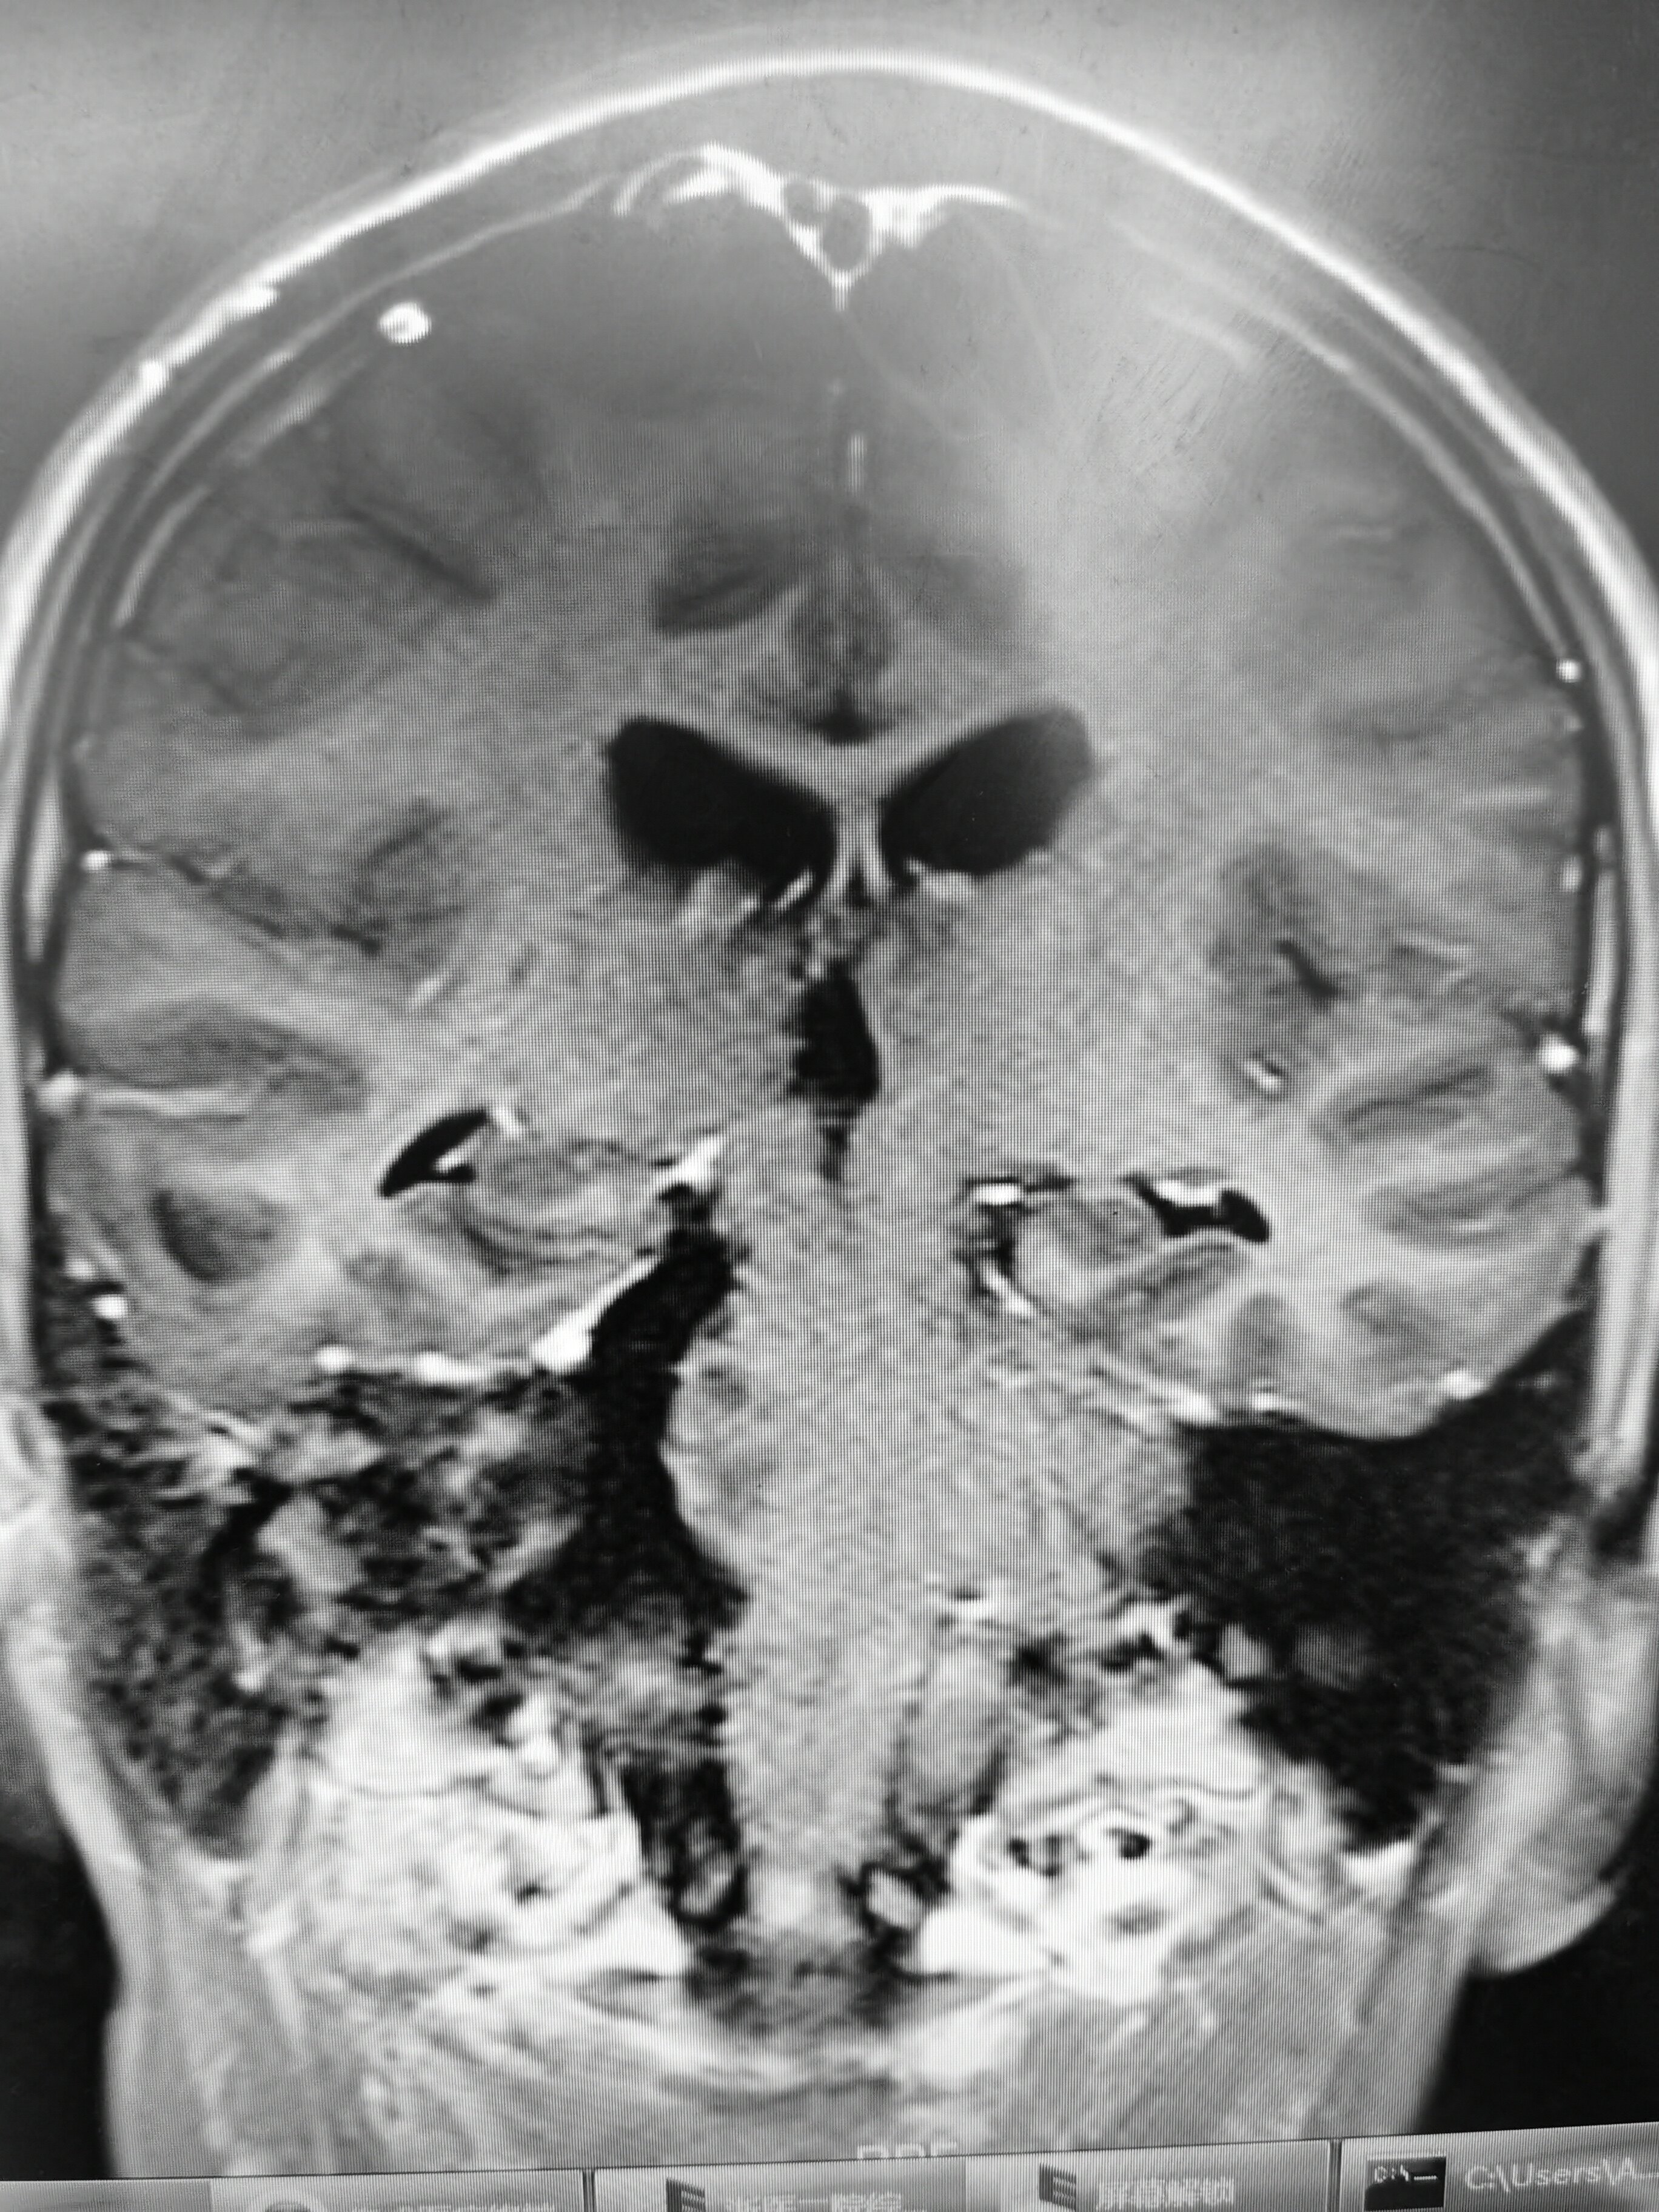

核磁共振显示一个巨大的听神经瘤,前后长3.4厘米,上下长3.

图片尺寸1000x658